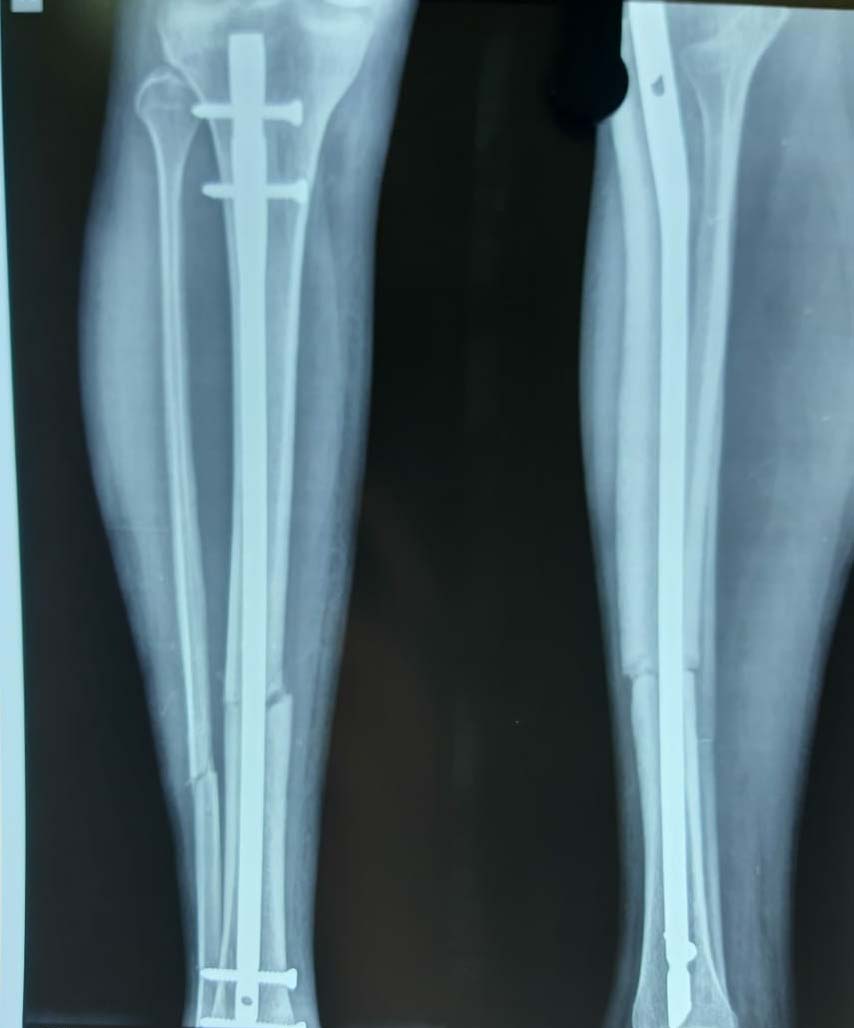

Trauma Fracture